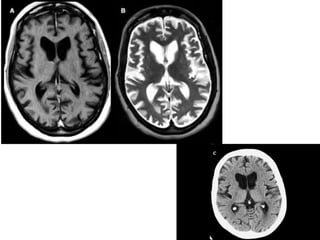

• #36 On brain MRI, T1-weighted (A) and T2-weighted (B) axial images show caudate atrophy and enlargement of the frontal horns. On CT, an axial image (C) from another patient shows similar findings.